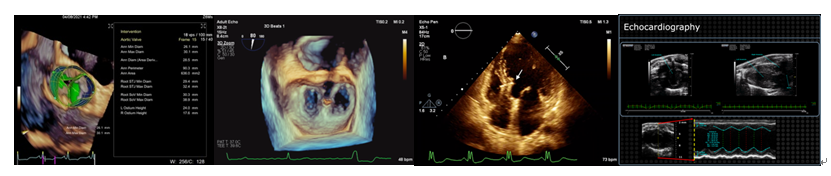

苏茂龙教授团队长期从事心血管超声影像学临床及科研工作,开展了大量的心血管疾病基础和临床研究,对心血管超声造影、实时三维超声心动图、计算机建模及心脏同步化、室壁瘤微创介入治疗、二尖瓣及主动脉瓣微创介入治疗的超声评估均取得了一系列研究成果。

结构性心脏病的三维经食管超声心动图影像学研究